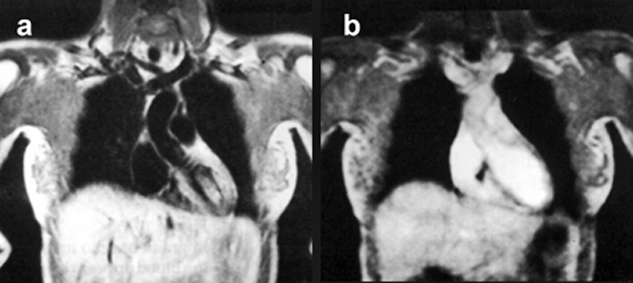

Figure 14-10:

Effects of blood flow upon signal intensity in a (a) spin-echo and a (b) gradient-echo pulse sequence.